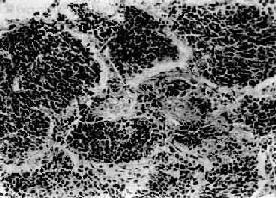

(2) 小细胞癌:发生率在肺癌中居第二位(临床统计在40%以上,尸检统计占15%~25%)。患者男多于女(20:1),发病年龄约在35~60岁。小细胞肺 癌亦多发生于肺中央部,生长迅速,转移较早,恶生度高,5年存活率仅1%~2%。小细胞癌的癌细胞很小,呈短梭形或淋巴细胞样,有些细胞呈梭形或多角型, 胞浆甚少,形似裸核。癌细胞常密集成群,由结缔组织加工分隔(图9-33)。有时癌细胞围绕小血管排列成假菊形团或管状结构。小细胞肺癌起源于支气管粘膜 和粘液腺内Kultschitzky细胞,是一种具有异源性内分泌功能的肿瘤。

小细胞肺癌

图9-33 小细胞肺癌

短梭形癌细胞平行排列,群集成团(燕麦细胞型)